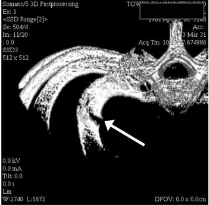

진단은 물론 X-ray 나 CT, bone scan 같은 영상검사로 하게 되지만

외상의 골절과는 다르게 여러개의 뼈가 부러지는 형태가 아닌 단일뼈가 부러지는 형태의

피로골절 형태의 골절이 생기는 경우가 많습니다.